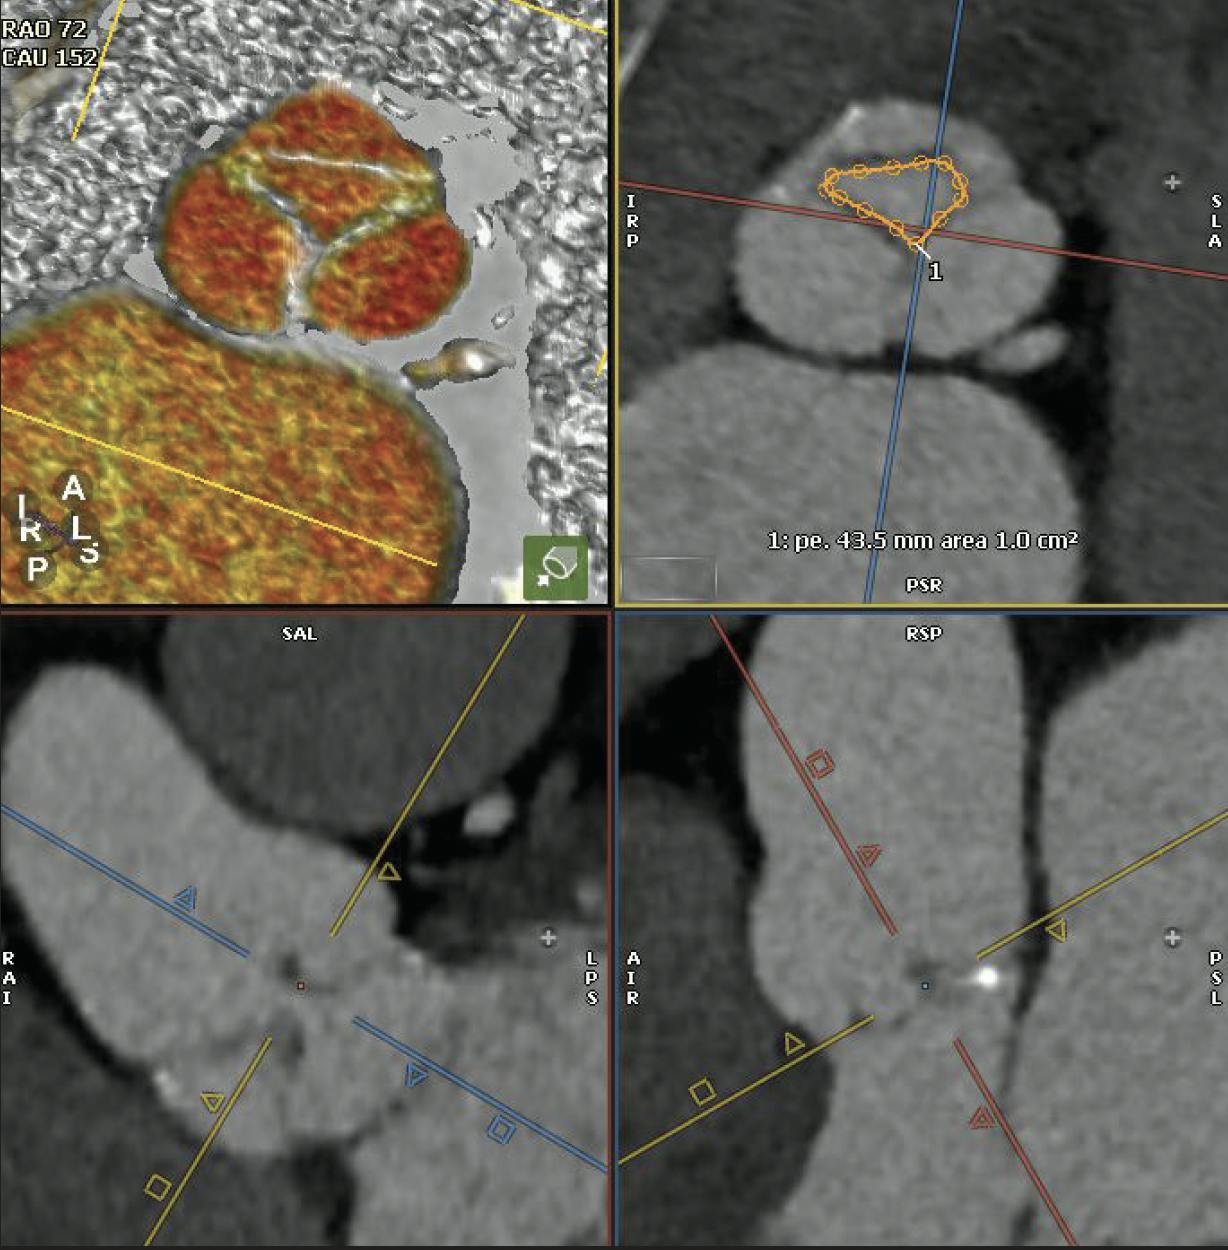

Although retrospective electrocardiography-gated functional CTA is used less commonly for AR assessment, it offers superb anatomic delineation of cardiac structures. Multidetector CT (MDCT) can measure the anatomical regurgitant orifice area through multiplanar reconstruction (MPR) techniques, providing insights into the mechanism of AR along with quantification of AR severity (Figure 1). MDCT is particularly useful when TEE or TTE provides equivocal results, when CMR is not available, or when surgical planning necessitates precise anatomic data.

Figure 1. Quantitative assessment of the anatomic regurgitant orifice area by CTA using multiplanar reconstruction.